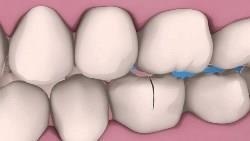

Soiurile de fisuri dentare

- Înclinat.

- Orizontală.

- Verticală.

- Fisurile din interiorul dintelui.

fisura dinte Înclinat centrează pe diagonală. În cazul în care o fisură nu este îndepărtată în timp util printr-un tratament stomatologic, rezultatul va fi dezamăgitor. Unghiul așchie al coroanei dintelui. De obicei o astfel de fisură tratată viniringa metodă.

Fractura orizontală intersectează altele asemenea ca ecuator dinte intersectează glob. fisuri orizontale, în cazul în care acestea nu sunt tratate, se termină întotdeauna clivaj. Ce cantitate de structura dintelui se pierde depinde de locația fisurii. Dacă fisura este situat sub zona de guma sau muchia de tăiere, în timp ce volumul țesutului pierdut este neglijabil, iar pulpa nu este afectată. În cazul în care fisura se află mai aproape de gâtul dintelui, apoi, ca rezultat al întregii clivaj coroana a dintelui se va pierde și va dezvălui pulpa. În acest din urmă caz, restaurarea dinților are o mulțime de probleme ca medic și un pacient și, astfel în mod substanțial se va lovi pe portofel.

O fisură verticală este aranjată paralel cu peretele lateral al dintelui și dinte se divide in doua parti. Dacă o astfel de fisură a fost văzută pe dinte, probabil, în procesul de inclus nu numai coroana, dar, de asemenea, rădăcina dintelui. În cazul în care fisura se execută pe toată lungimea dintelui de la marginea de taiere a foramen apical radacina, un dinte nu poate fi vindecat conservator. În acest caz, singura opțiune de tratament este de a elimina dintele. Daca un dinte este spart, nu este întreaga lungime, apoi a avut loc un tratament endodontic și dinte întărirea coroanei artificiale.

Fisura din interiorul dintelui este cel mai insidioasă, deoarece nu este văzut vizual. Aceste fisuri sunt identificate prea târziu, atunci când se întorc într-o fractură.